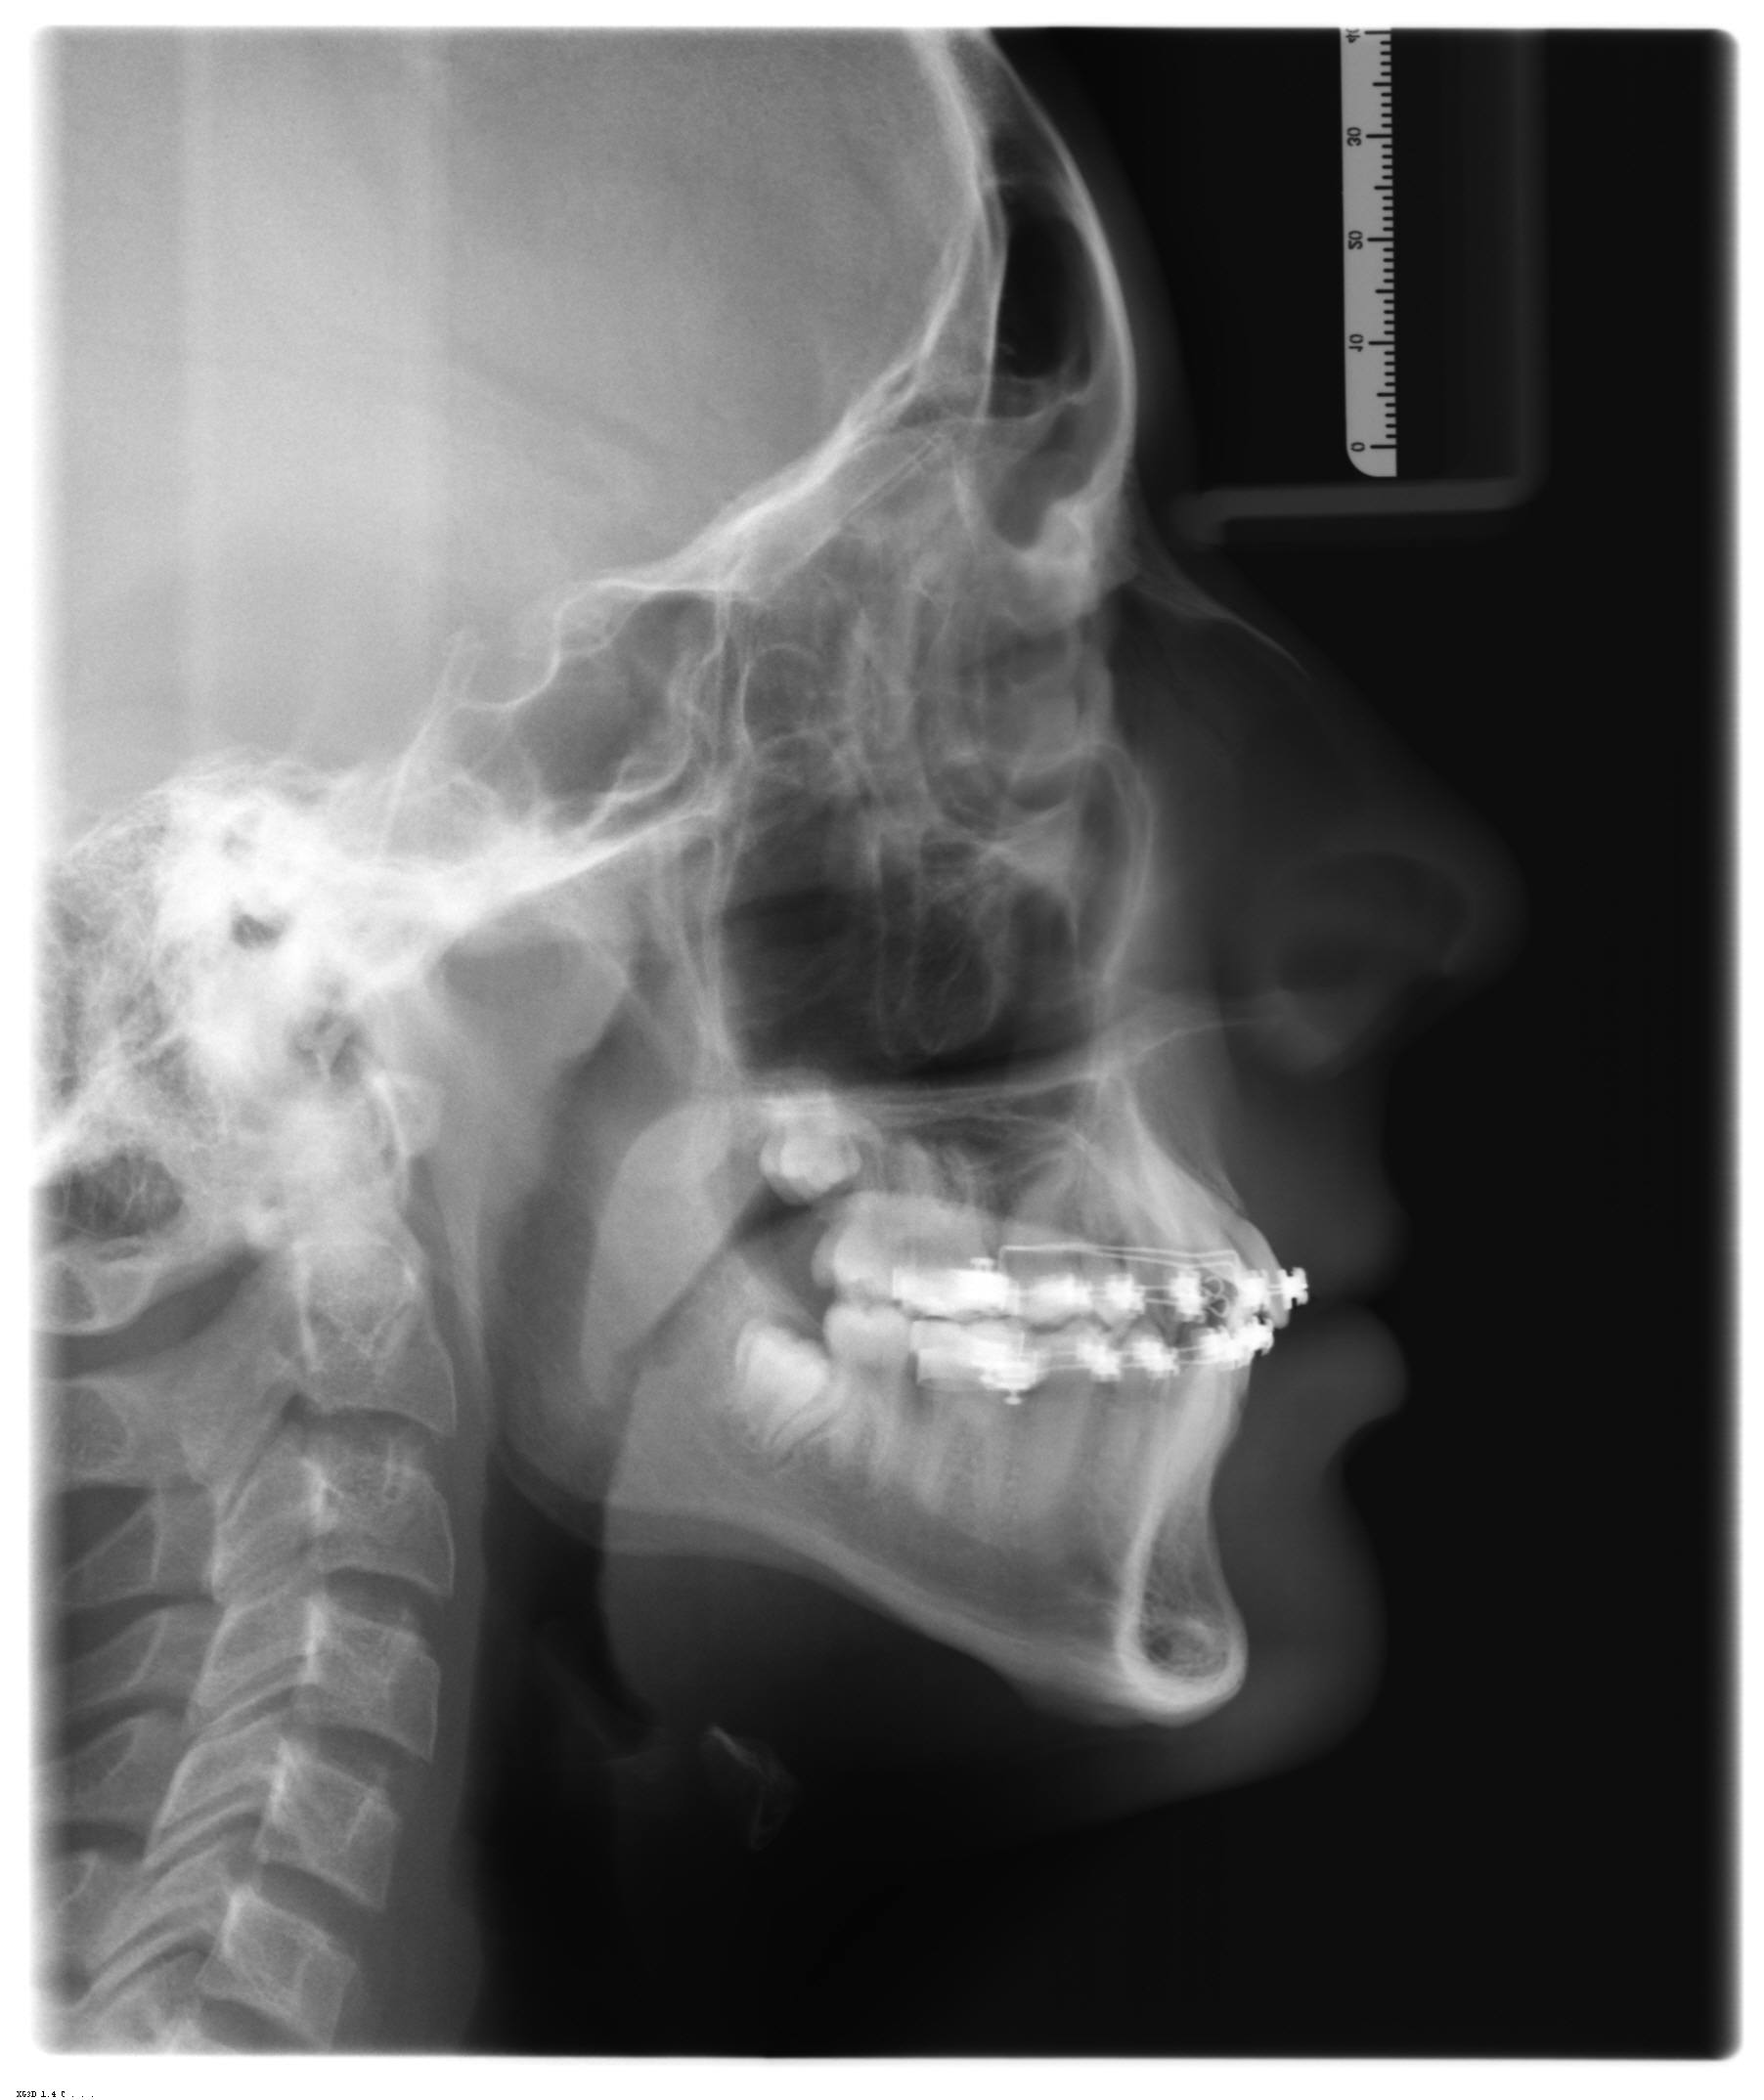

Telerradiografia

Indicação e Legenda de telerradiografia em norma Lateral

Principais indicações:

Observação do espaço naso-faríngeo, avaliação do padrão dento-esquelético facial, crescimento do crânio e face pela sobreposição de traçados e também planejamento do tratamento ortodôntico ou ortopédico.

Legenda:

- Seio Frontal

- Osso Nasa

- Cavidade Orbital

- Processo Zigomático da Maxila

- Seio Maxilar

- Sela Turca

- Cabeça da Mandíbula

- Espinha Nasal Anterior

- Espinha Nasal Posterior

- Palato Mole

- Parte Nasal da Faringe

- Parte Oral da Faringe

- Laringo - faringe

- Sínfise da mandíbula